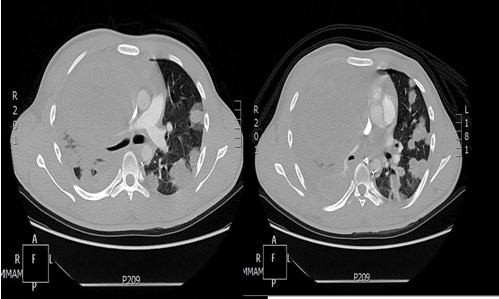

After discharge by one week, the patient admitted again from the emergency with shortness of breath, spiral CT scan of chest was done to rule out pulmonary embolism that was negative, but there was evidence of disease progression in comparison to the previous study (Figure 4).

Figure 4: Spiral chest computed tomography scan with contrast before 2nd cycle of chemotherapy to rule out pulmonary embolism.